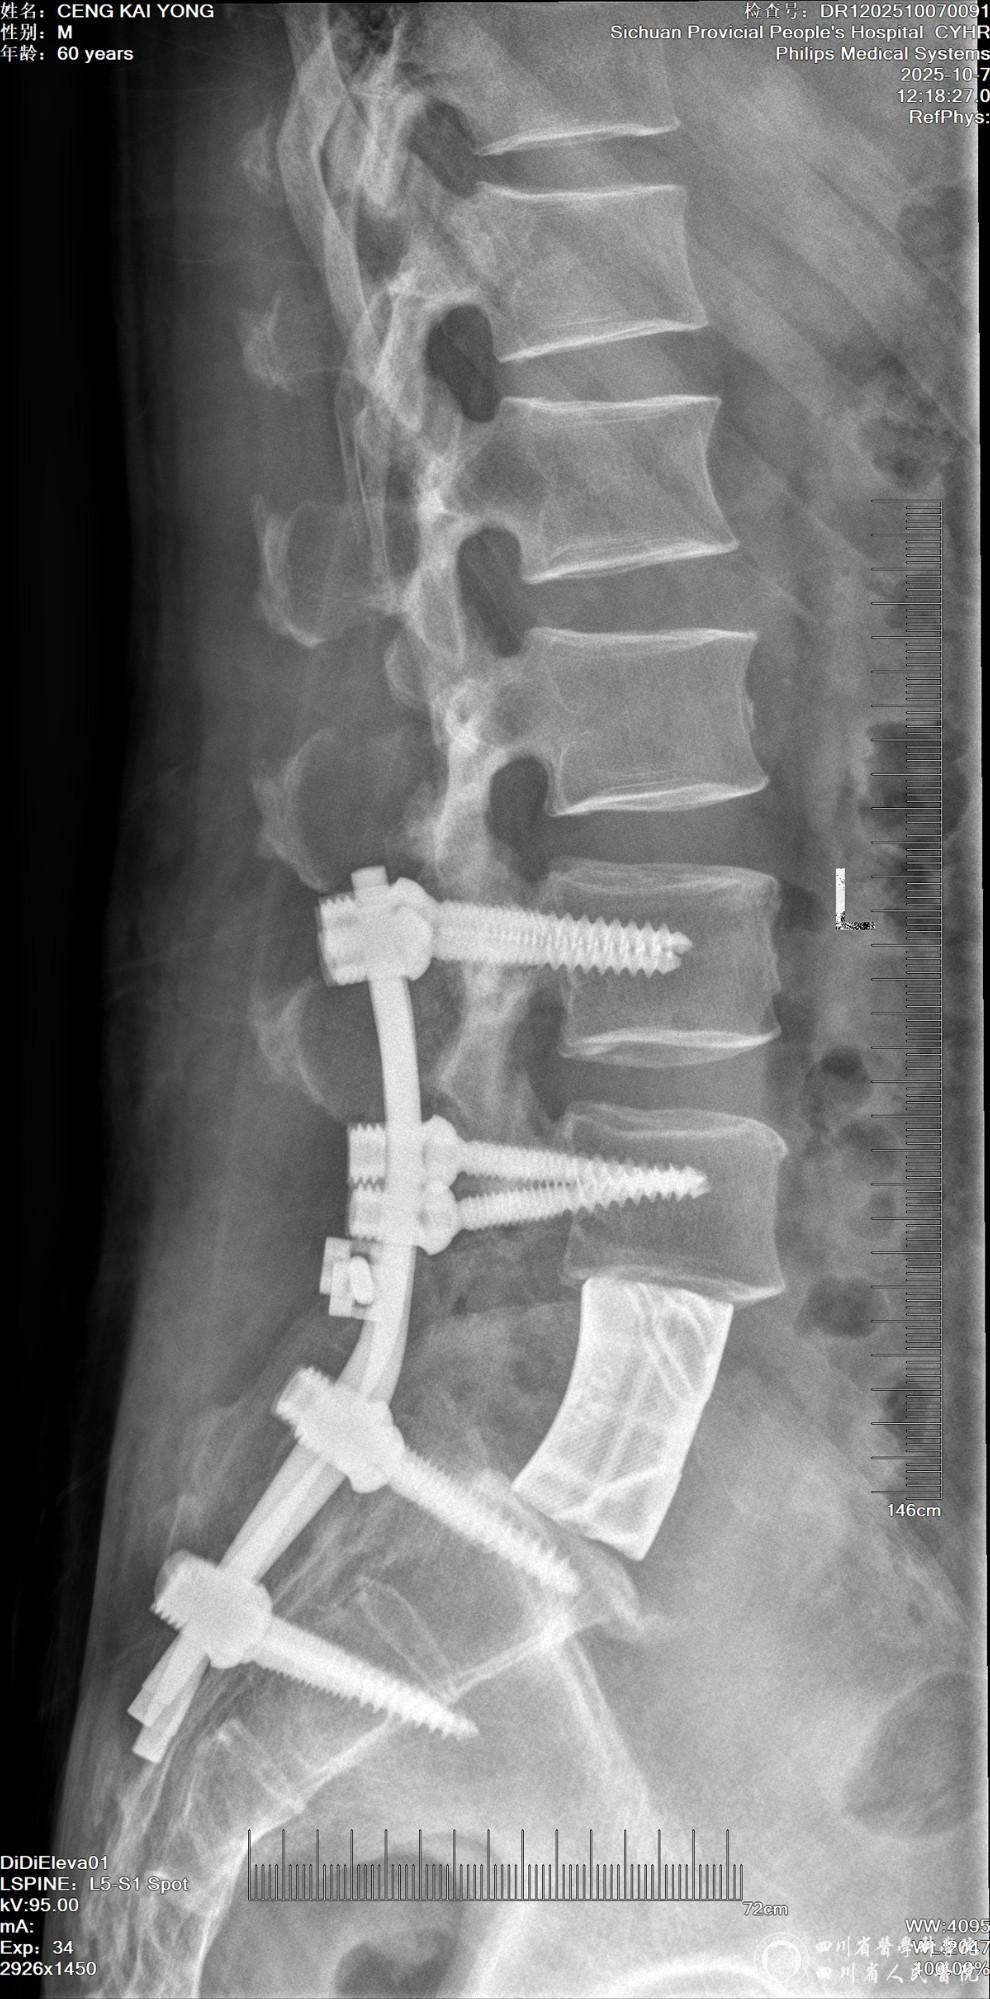

小心翼翼剥离肿瘤与周围血管的粘连,精准避开重要血管分支,严防出血风险;再精细分离受肿瘤压迫的神经,确保神经功能不受损伤;完整切除病变的椎体及肿瘤组织,彻底解除压迫。随后植入椎弓根螺钉与患者腰椎参数匹配的3D打印人工锥体,完成脊柱稳定性重建。整个手术操作精准到毫米,团队配合默契,出血量远低于预期,重要血管与神经功能完好。

手术效果立竿见影!术后困扰患者数月的剧痛彻底消散。术后第二天,患者在协助下成功坐起,“真没想到还能像正常人一样走路,太感谢俞主任了”,患者满是惊喜,家属多次向团队致谢。